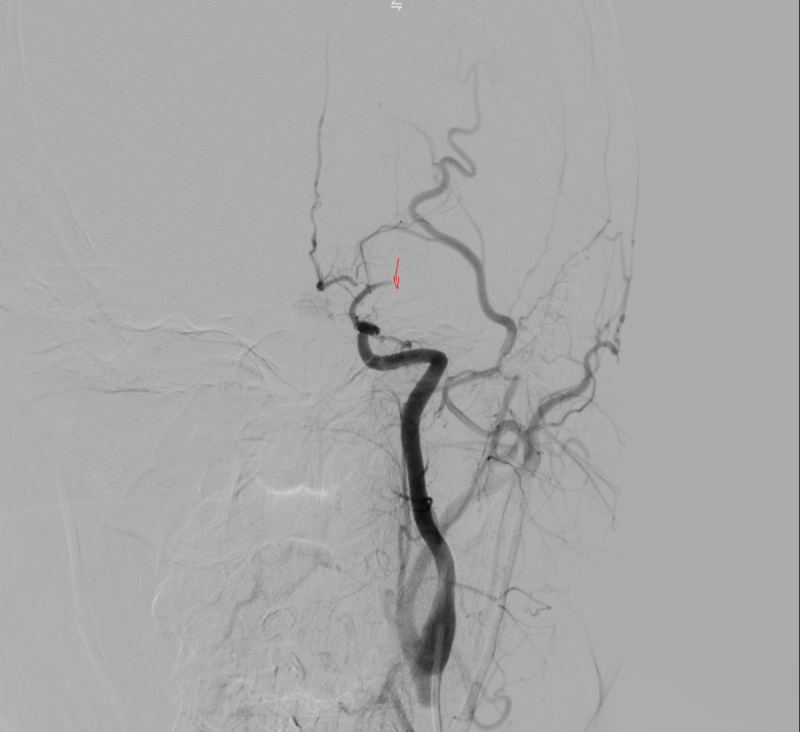

Kết quả chụp DSA xác định tắc động mạch não giữa trái đoạn M1 do hẹp nặng. Kíp can thiệp đã tiến hành nong bóng tái thông mạch máu, khôi phục dòng chảy lên não thành công.

Hình ảnh: DSA trong can thiệp hẹp nặng M1

Hình ảnh: Chụp DSA trước can thiệp thấy tắc M1 trái